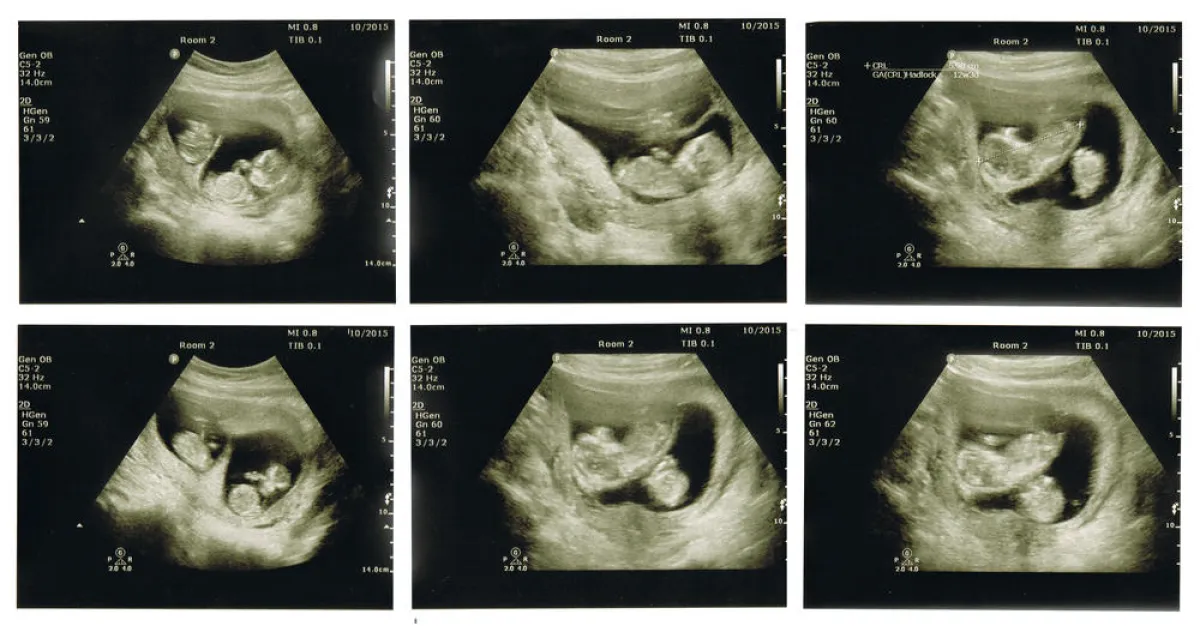

• الانقسام الجزئي ويحدد بالموجات فوق الصوتية، ويستلزم راحة الحامل في السرير.